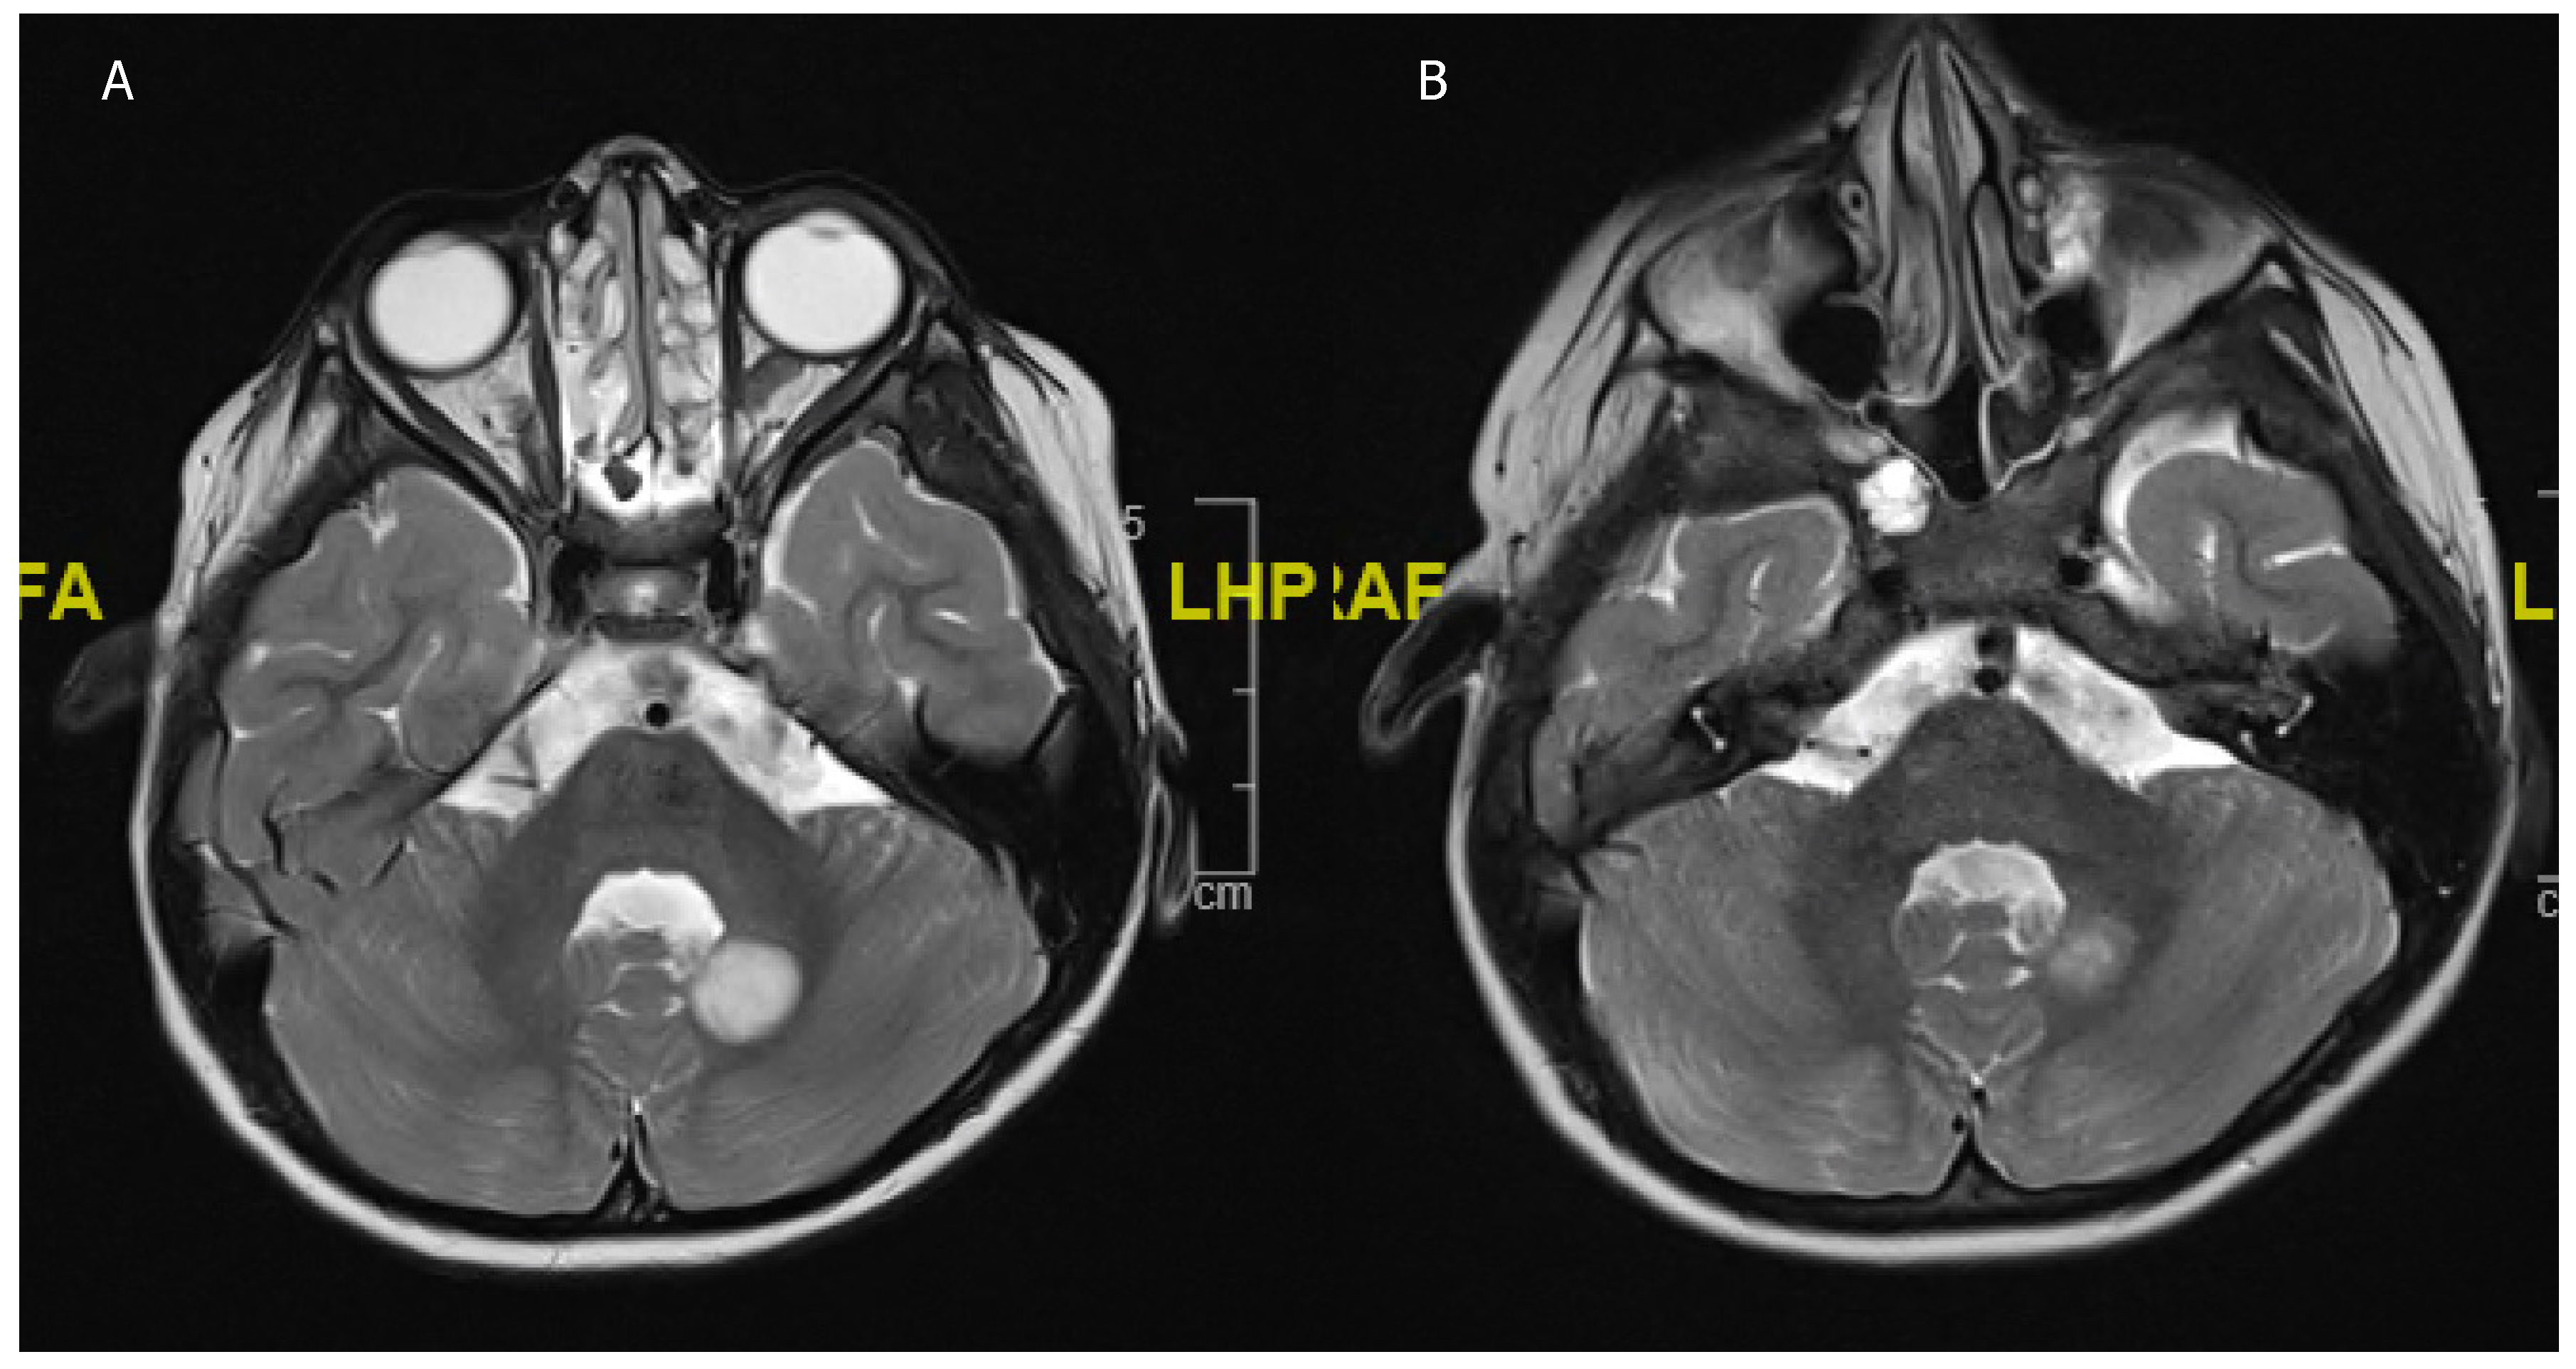

Figure 3. An 11-year-old boy presenting with headaches and blurry vision. (A) Preoperative MRI scan showing a 6.1 × 4.0 × 3.4 cm T2 hyperintense and contrast enhancing (not shown) lesion suggestive of (non-NF) optic pathway glioma. (B) Postoperative MRI scan after partial resection with tumor rest in the optic pathway. Histology confirmed a BRAF600 mutated pilocytic astrocytoma. (C) Follow-up MRI scan after 4 weeks of MEK inhibitor treatment showing a nearly complete regression of the tumor.

Most pLGGs, even if they do not include one of the typical driver mutations, contain mutations affecting the MAP-Kinase pathway. This could make them possible targets for BRAF/MEK inhibitor therapy [64,76]. The two best-known BRAF/MEK inhibitors currently being investigated in pLGG are selumetinib and trametinib, with skin toxicity being the most frequently described adverse event of the treatment [74,78,82,83] (Figure 3).

PLGGs harboring KIAA1549-BRAF mutations are more responsive to BRAF inhibitors than BRAFV600E-mutated tumors [77]. A recent phase II trial for recurrent or progressive pLGG showed that patients treated with selumetinib had a two-year PFS of 78 ± 8.5% and that visual fields and acuity improved or remained stable in the majority of patients, concluding that selumetinib leads to prolonged disease stability [78]. A current prospective trial investigating trametinib in pLGG is ongoing; the results are yet to be published (NCT02124772). In two retrospective cohort studies with a total of 28 patients, 12 patients showed a minor or partial response, while 16 patients achieved stable disease when treated with trametinib [82,83]. In one of the studies, around a third showed disease progression over the course of treatment, while in the other cohort, all the patients achieved disease control [82,83]. There is currently a trial ongoing comparing MEK/BRAF inhibitors to a CV regimen in pLGG, focusing on overall response rate (ORR), PFS, and OS; the results are yet to be published (NCT02684058). Some studies have observed a paradoxical activation of tumor growth with BRAF/MEK inhibitor treatment, especially in KIAA1549-BRAF- and NF-1-mutated pLGG [64,84]. This might prompt even more specific therapies for the distinct mutations [84]. Another challenge after the successful initiation of BRAF/MEK inhibitors is to decide when to discontinue treatment, weighing the risk for tumor recurrence and treatment side effects against each other. Tumor progression is often observed after the termination of BRAF/MEK inhibitors [82,83]. Target therapy trials for LGG are currently only carried out within the pediatric population.